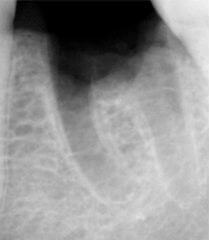

Проблема. Глубокая кариозная полость

Решение. Каналы были очищены, подготовлены к пломбированию, сделан дентальный снимок с пломбировочным материалом.

Запломбированы корневые каналы зуба. Зуб подготовлен к дальнейшему лечению.